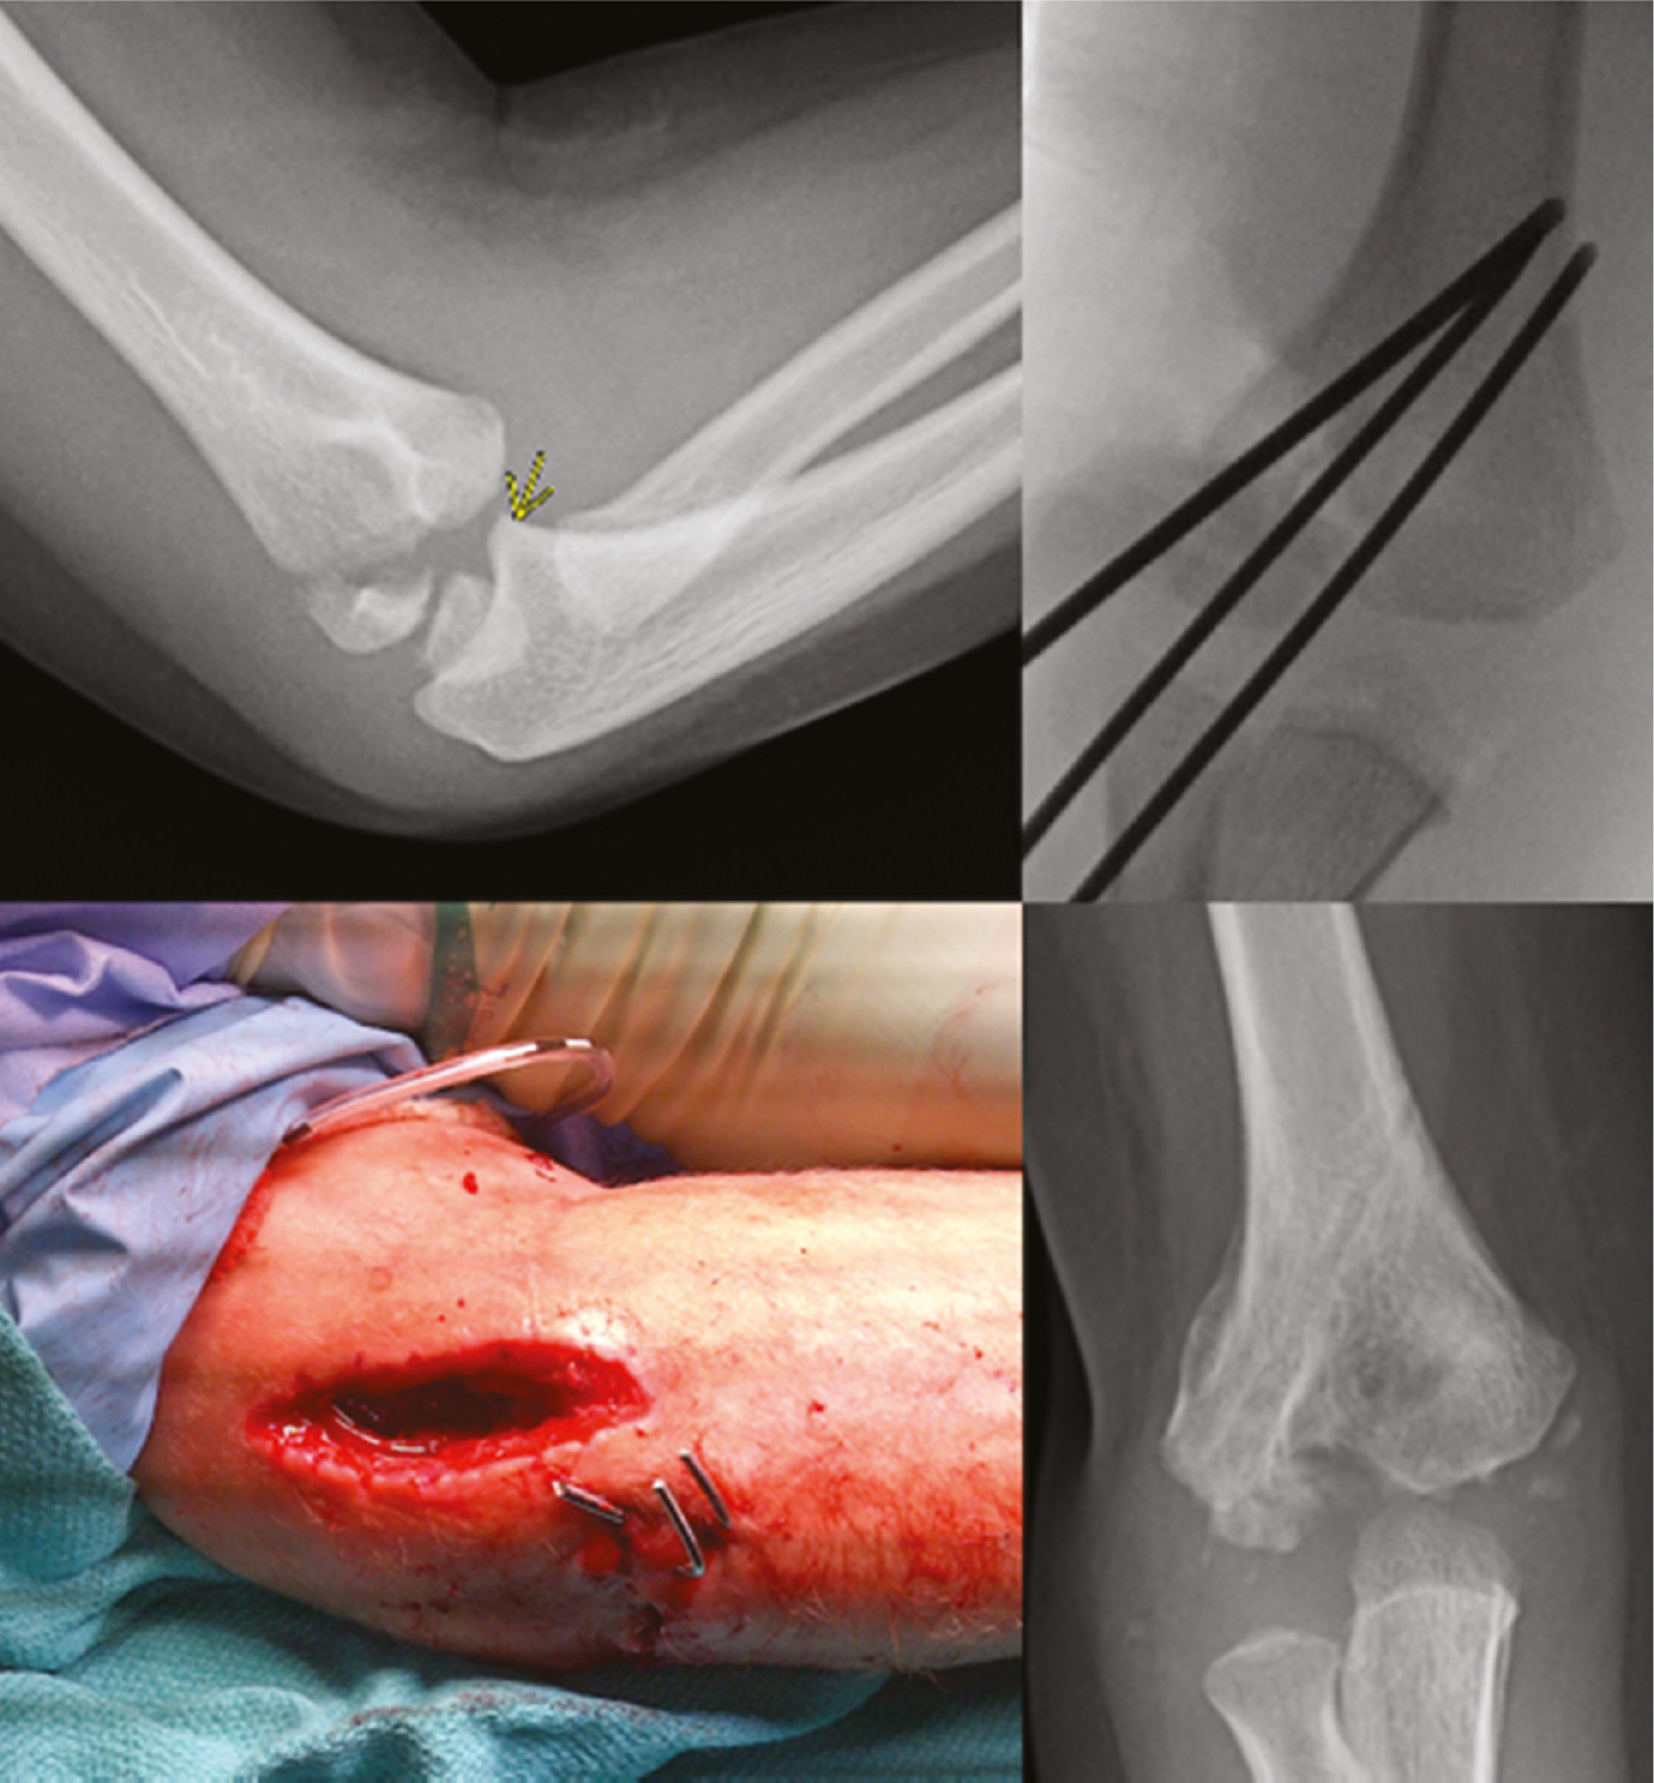

Occasionally, anatomic reduction of the articular surface will result in acceptable metaphyseal gapping. The surgeons’ focus should remain on reduction of the articular surface, and malreduction at the joint line can occur from the surgeon’s desire to anatomically reduce the metaphyseal component of the fracture (Figures 12 and 13).

Figure 12. Articular step-off is noted in this Milch Type 1 fracture.

jposna2023632_fig12.jpg

Figure 13. The fracture is reduced at the articular surface and pinned. Use of an absorbable suture around the wires and through the metaphysis can reduce metaphyseal displacement.

jposna2023632_fig13.jpg

Two or three K-wires are then inserted in a divergent fashion across the fracture site. Utilizing a two-pin construct, one pin should serve as the articular pin aiming for the medial epicondyle in a lateral to medial direction. The second pin should be directed up the lateral column with a goal divergence angle of at least 60 degrees if possible5 (Figure 14).

Figure 14. AP and lateral fluoroscopic images showing reduced and pinned lateral condyle fracture. Notice the ideal positioning of the two-pin configuration.

jposna2023632_fig14.jpg

One complication that can occur from lateral condyle fracture pinning is septic arthritis developing from pin tract infection. It’s prudent to remember that pins used to stabilize these fractures are very commonly intraarticular; thus, pin tract inflammation/infection can lead to septic arthritis. For this reason, these pins are ideally removed within 4 weeks regardless of radiographic signs of healing (Figure 16).

Figure 16. This 5-year-old boy with a lateral condyle fracture developed septic arthritis and despite eventual healing, has signs of central humerus necrosis with an unknown natural history.

jposna2023632_fig16.jpg